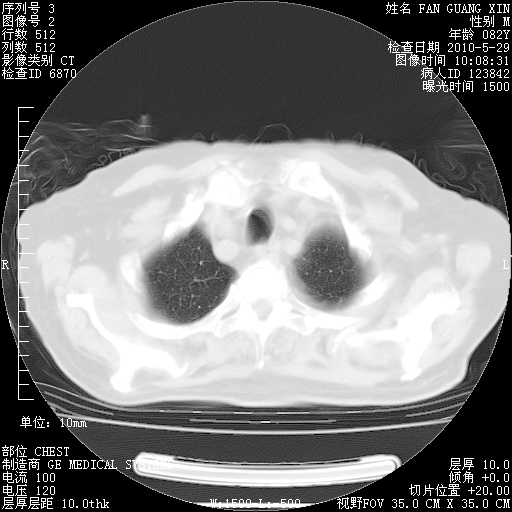

再治疗10天后的肺部CT

再治疗10天后的肺部CT 纵膈窗